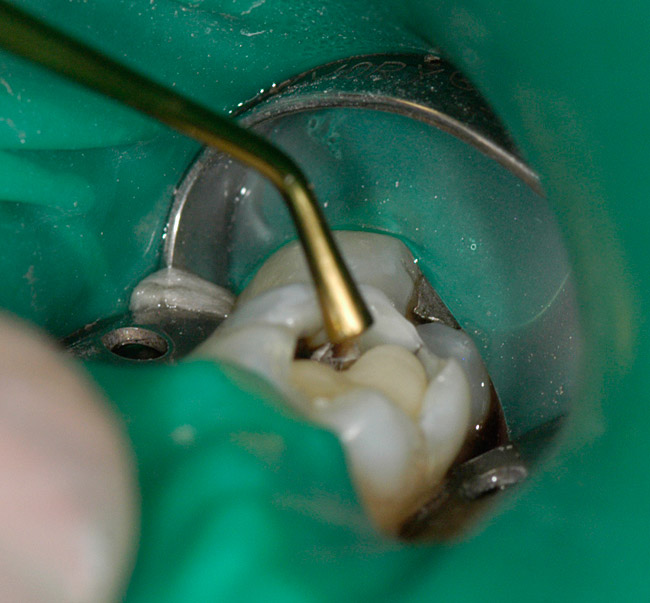

Figure 2  Shows a view of the tooth isolated by the rubber dam. The preparation is complete and the tooth has been total etched for 5 seconds and thoroughly rinsed with water for 15 seconds. The tooth has been blotted dry and a flowable base is being bulk-filled into the deepest portions of the cavity preparation.

Figure 2

When all caries has been removed, the cavity preparation should be rinsed with the air/water syringe for 10 seconds and dried. Using a 32% to 37% phosphoric acid gel, the dentin portions of the cavity preparation should be etched for no more than 5 seconds to “cleanse” the surface of the dentin. An air/water syringe is used for 15 seconds to neutralize and remove any remaining etch material.27 The exposed dentin areas of the preparation are then carefully moistened using a cavity desensitizer such as Gluma® (Heraeus Kulzer) a formula of 5% glutaraldehyde and 35% HEMA (hydroxylethyl methacrylate) in water. The Gluma is placed using a small, disposable, flocked tip applicator.28 The dentin is left slightly moist, and is then based out using glass-ionomer cement (Figure 2). Glass-ionomer cement has superior biocompatibility. Glass ionomer has a similar coefficient of thermal expansion to dentin and it supplies fluoride to help remineralize any surrounding tooth structure it may contact. Glass-ionomer cements remain dimensionally unchanged during their polymerization process and, therefore, do not place any stress on the fluids of the dentinal tubules.29